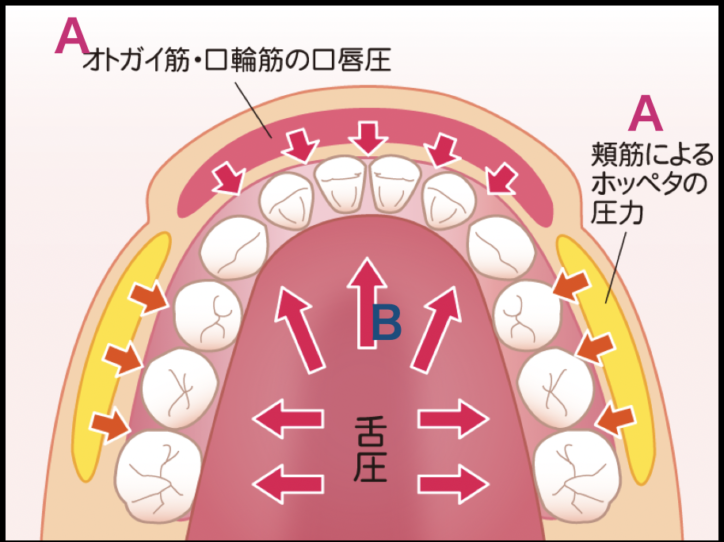

子どもの歯並び予防の考え方(14)~歯並びの成り立ち(バクシネーターメカニズム)〜

2024.06.01

かいり歯科クリニックの戸田です。

今回は、子どもの歯並び相談の際に保護者の方の疑問である

『歯はなぜその位置にあるの?』

に関して簡単にご説明させて頂きます。

上記の図をご参照下さい。歯のアーチ(歯列)は

A: 顎の筋肉(オトガイ筋)やお口の周りの筋肉(口輪筋)とホッペタの筋肉(頬筋)による外から内への圧力

B :舌の筋肉による内側から外側へ圧力

が、常にかかってます。つまり

A :口唇と頬による内側への圧力 VS B: 舌による外側への圧力

このようにして歯列は、両方向から圧力を受けることによって、安定が保たれています。

そしてこの圧力が不足したり、本来かかるところではない部位に圧がかかったりすると顎の正しい成長が阻害されたり、歯並びの乱れへと繋がっていきます。

このような歯並びと筋力の関係を専門用語で「バクシネーターメカニズム」と呼びます。